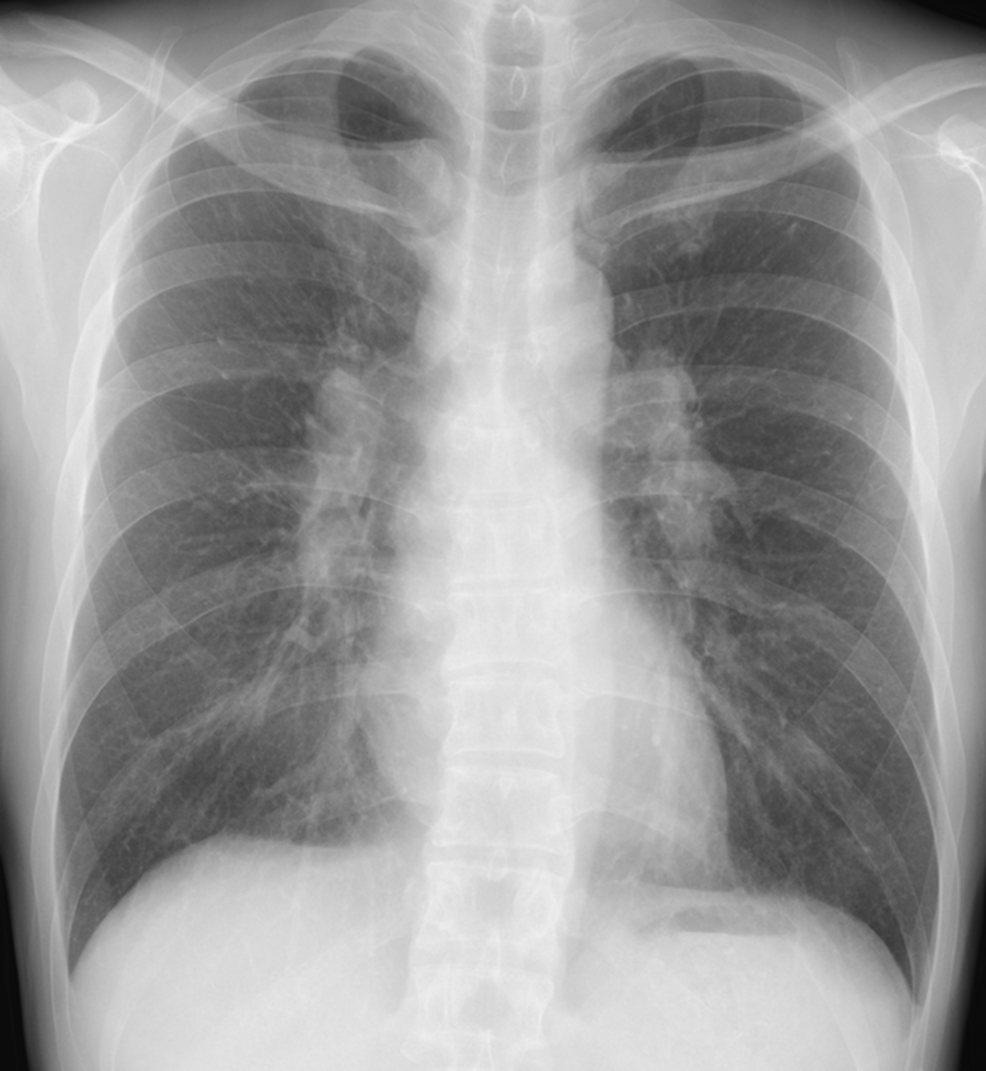

——そして胸部CT——

もろもろ検査→電子タバコの肺障害と診断!